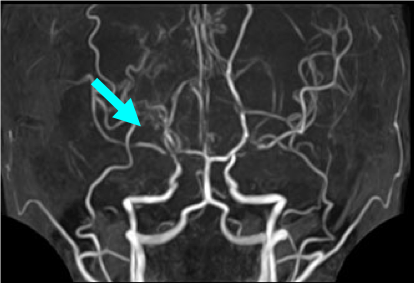

術前のMRA画像です。矢印の部位で動脈が狭窄、閉塞しています。